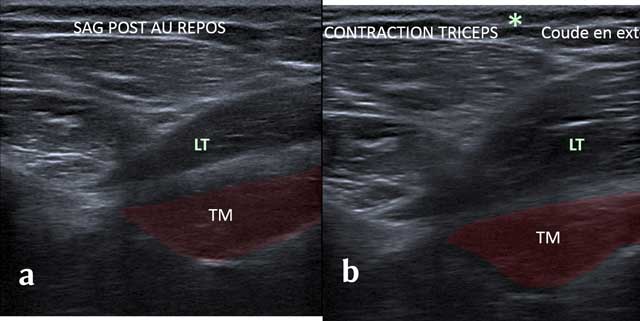

Figure 10

Sagittal view without (a) and with (b) Tricepscontraction with elbow in extension. TM: Teres Major, LT: long head of the triceps.